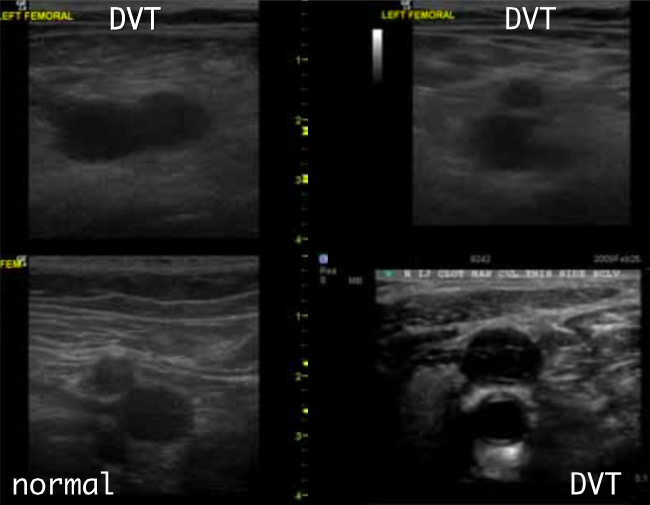

How do you assess for DVT?

Find the vessel and try to collapse it. If the vein is not compressed by the time the artery is compressed you know the clot inside the vein is holding the walls open.

Where to check for LE DVT

Femoral and popliteal regions